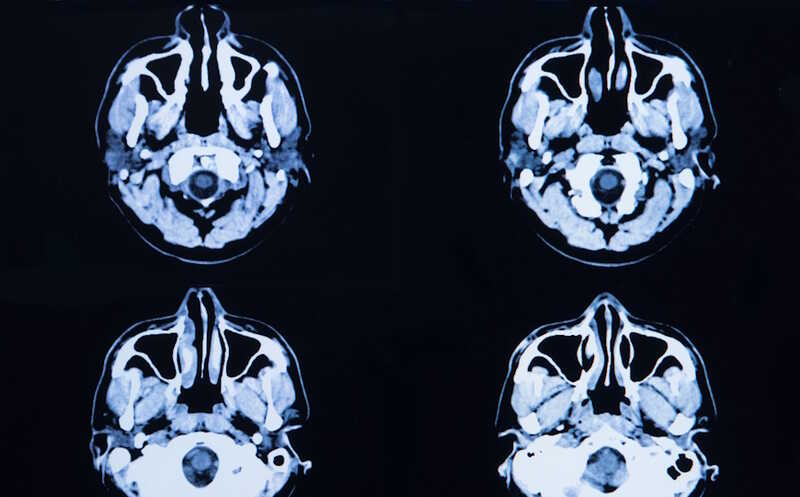

На долю женщин приходится две трети случаев болезни Альцгеймера (БА). По сравнению с мужчинами у них более выражены тау-патология и снижение когнитивных функций, а также повышена уязвимость при наличии неблагоприятного аллеля ε4 аполипопротеина Е (APOE ε4). Накопление α-синуклеина при БА встречается примерно у половины больных. Однако до сих пор нет данных, влияет ли пол на темпы накопления тау-белка при α-синуклеинопатии. Ученые из США проанализировали данные позитронно-эмиссионной томографии (ПЭТ) и содержание α-синуклеина в спинномозговой жидкости (СМЖ), чтобы определить половые различия в синуклеинопатии и накоплении тау-белка.